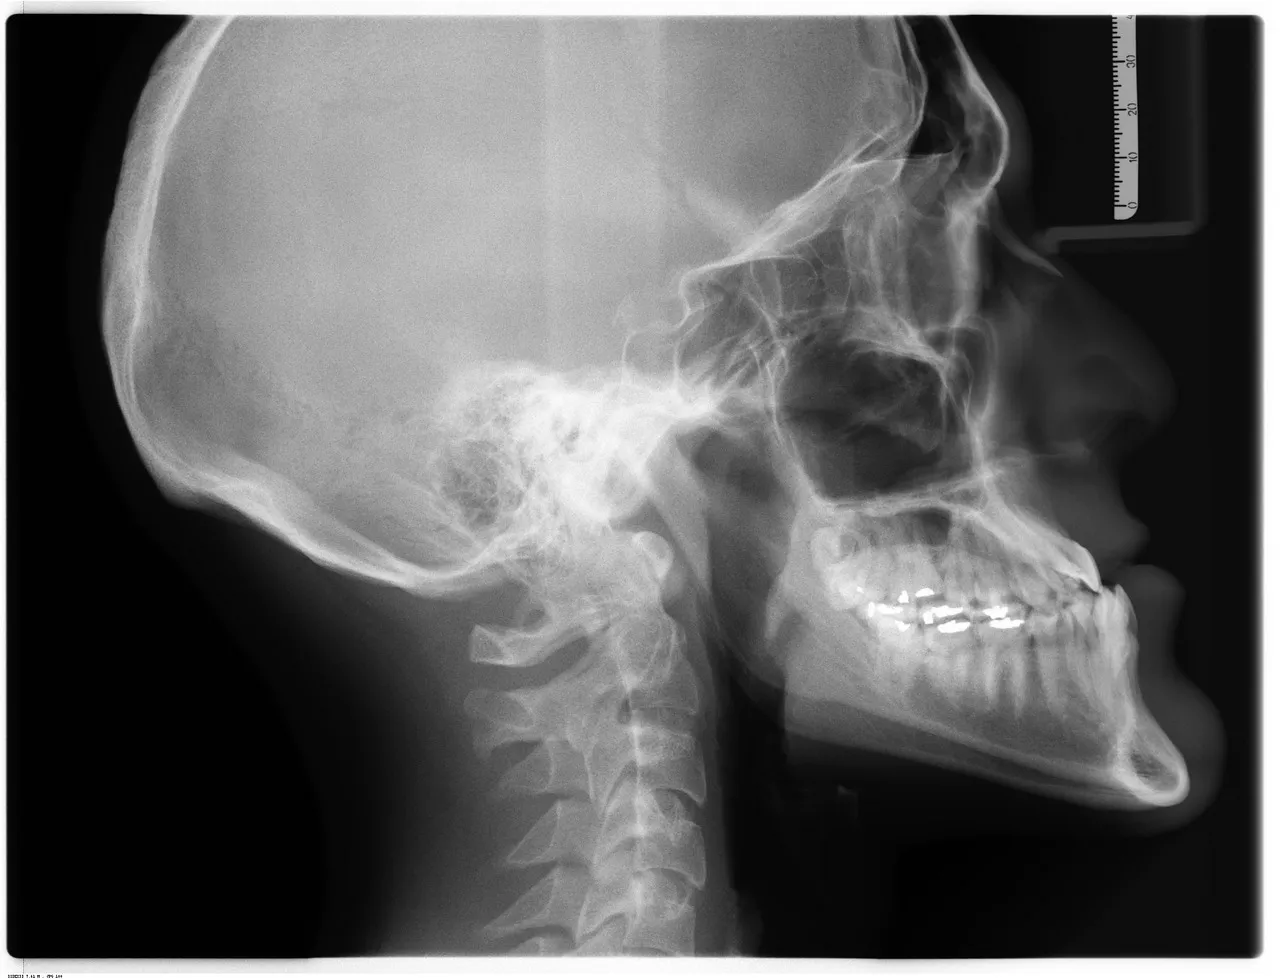

- 3D CBCT Scanning: Reveals complex root anatomy invisible on traditional X-rays

- Day 1: Diagnostic X-ray/CBCT scan, clinical examination, local anesthesia, pulp removal, canal cleaning and shaping